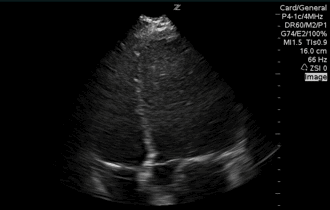

QA of the Day, Sono Stuff QA of the Day #pocus #ultrasound #foamed #foamus Date: July 7, 2016Author: Mike 0 Comments Nice apical 5ish. Let’s perfect it and add some depth. Share this: Share on X (Opens in new window) X Share on Facebook (Opens in new window) Facebook Like Loading...